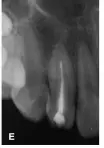

25個月后復(fù)診:X線片顯示i根尖區(qū)暗影消失,主根管根尖基本閉合,根尖愈合(圖1E)。復(fù)診時發(fā)現(xiàn)同為牙中牙的2牙體稍變色,牙髓熱測試無反應(yīng),診斷為2牙髓壞死,2開髓后可探及內(nèi)陷根管的根尖止點(diǎn),測量工作長度為22mm,25~30號擴(kuò)挫后Vitapex充填內(nèi)陷根管,磷酸鋅水門汀封洞(圖1F),調(diào)牙合消除2咬合干擾,囑以后每隔半年復(fù)診1次,適時行內(nèi)陷根管的根管治療。

圖1E:治療后25個月4主根管根尖閉合;F::2 Vitapex充填內(nèi)陷根管